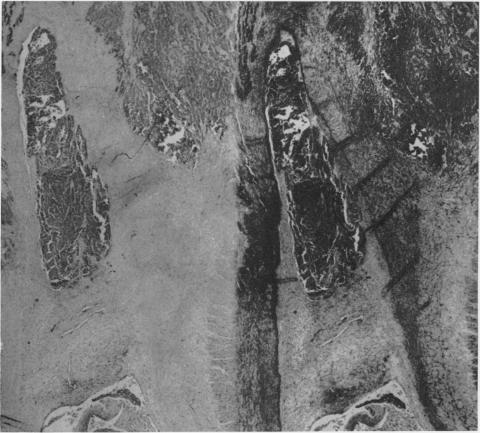

BRONCHOGENIC CARCINOMA: A STUDY OF CASES TREATED AT JOHN HOPKINS HOSPITAL FROM 1933-1958.

Ann Surg. 1965 May;161(5):674-87. doi: 10.1097/00000658-196505000-00005.